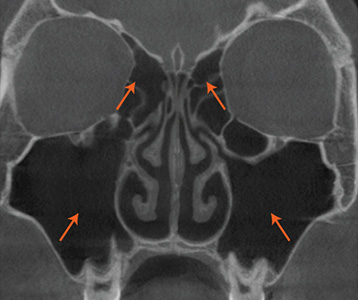

재수술 후